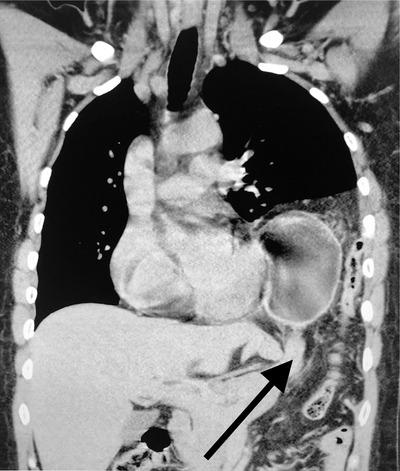

Woman with nausea and abdominal pain after a motor vehicle collision.